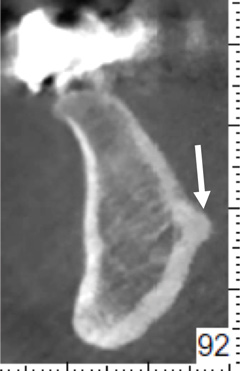

Fig 8. Deficient ridge contour at the osseous crest: cross-sectional view. This ridge (arrow) is not wide enough to receive an implant unless additional bone grafting is done to accommodate the implant’s width or the bone is reduced to a widened part of the ridge suitable for implant insertion.

Figure 8